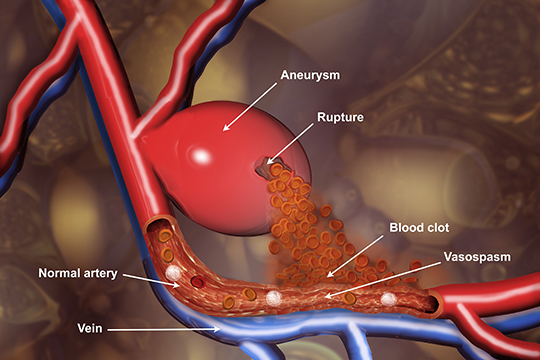

Снимки и иллюстрации микроаневризм сосудов головного мозга